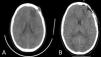

An 11-year-old boy presented with increased volume in the left frontal region, without neurological deficit or systemic symptoms. CT and MRI revealed an aggressive osteolytic lesion with perilesional oedema and intracranial extension.

Un niño de 11 años presentó aumento de volumen en la región frontal izquierda, sin déficit neurológico ni síntomas sistémicos. La tomografía y la resonancia magnética revelaron una lesión osteolítica agresiva con edema perilesional y extensión intracraneal.